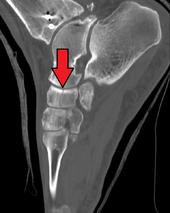

Fracture of the navicular bone

The human navicular is not a commonly broken bone.